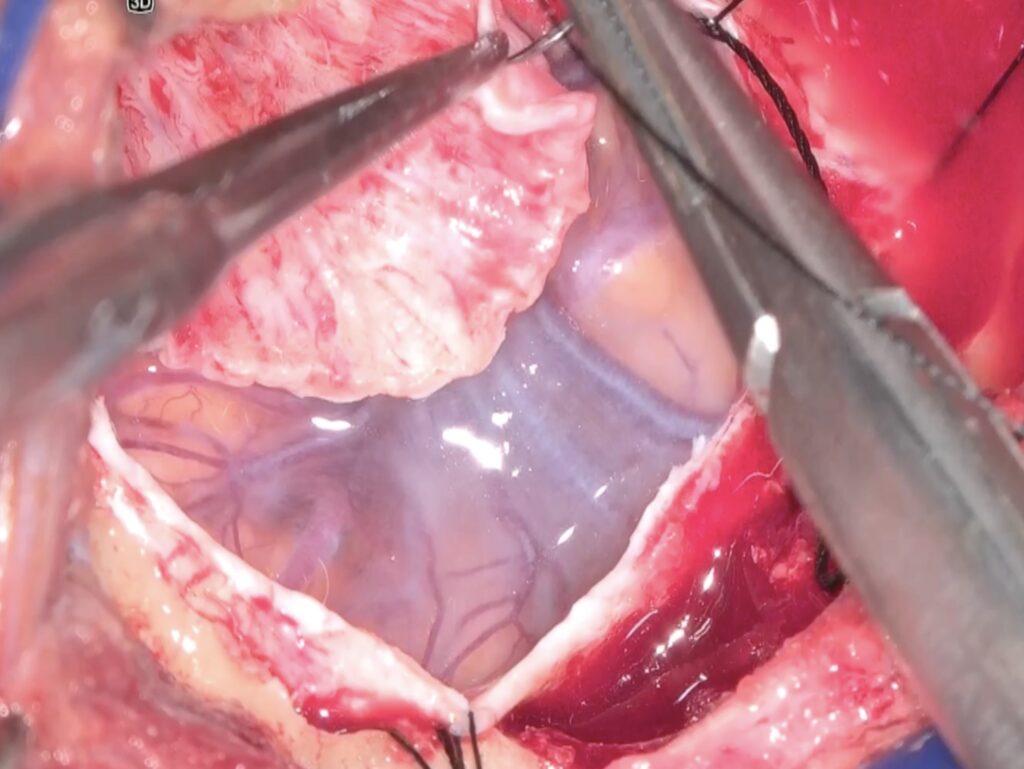

硬膜切開を行い、シルビウス裂を開けると動脈瘤が容易に露出されました。

案外 superior trunk M2の影になりM1が見えにくかったのですが、M2を避けてM1を確保しました。一時クリップで遮断してみましたがMEPに異常が見られませんでした。

動脈瘤に張り付いた小動脈をsharp dissectionにより剥がしネックを露出しました。